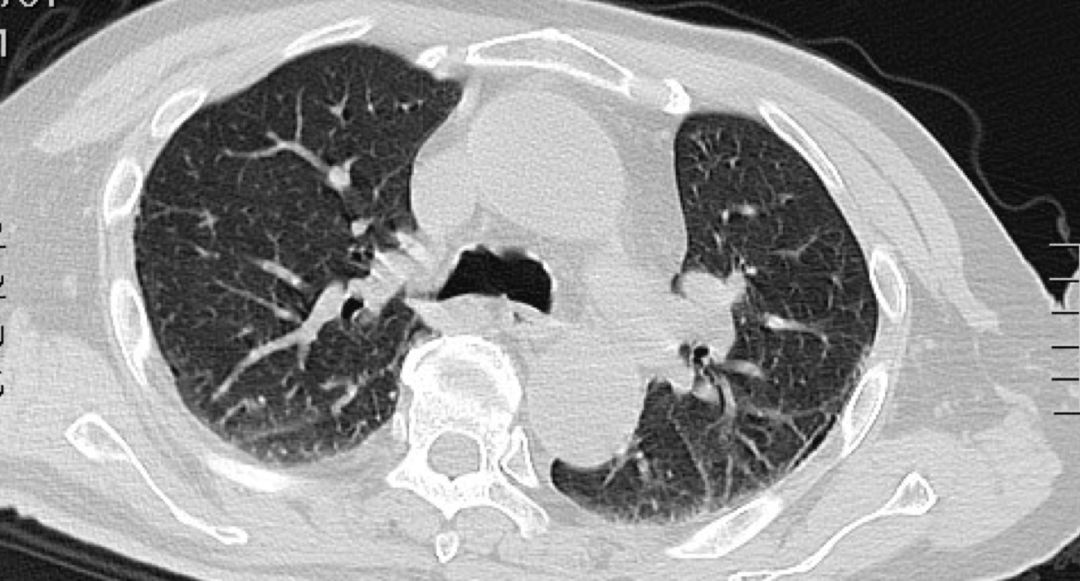

血Na133mmol/l,血常规:WBC 13.34*10^9/L,N% 91.3%,Hb 105.0g/L,PLT 237.0*10^9/L;CRP:15mg/L;心梗三项:高敏肌钙蛋白:0.016ng/ml↑,余正常;降钙素原:0.738ng/ml;心电图:1.窦性心律 2.T波改变(I、aVL、II、III、aVF、V4、V5、V6倒置)。 腹部CT(-),胸部CT如下。

该患者疾病诊断和病因究竟是什么?肺部感染吗?但患者肺部影像又没有看到显著感染征象,临床表现也不符合肺部感染,故肺部感染诊断不成立……患者高热、意识障碍伴有神经系统体征,诊断首先考虑中枢神经系统感染可能。